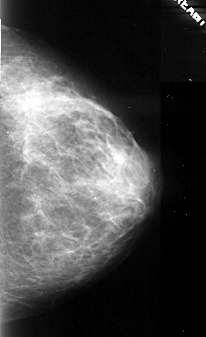

A_1105_1.LEFT_CC

LEFT_CC LINES 4741 PIXELS_PER_LINE 2821 BITS_PER_PIXEL 16 RESOLUTION 42 OVERLAY